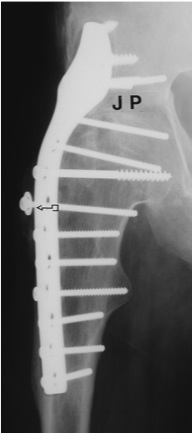

Extra-articular Intra-articular Combined intra-articular + anterior plate

Hip Fusion Cobra Plate Hip Fusion AP Hip Fusion 1Hip fusion 2

Fixation

- 150° DHS / 6.5 mm cannulated screws

- through joint into thick supra-acetabular area of ilium

- supplement with additional screws as necessary

Anterior plate onto lateral aspect of iliac crest